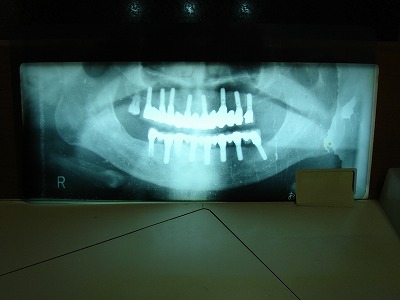

■代表的なインプラント治療

■使用インプラント

医院では、骨整形外科分野で40年余りの実績をもつスイスのストローマン(straumann)と

ITI(口腔インプラント学のための国際チーム)で共同開発されたITIインプラントを使用しています。

●特徴

手術2回式のインプラントであれば、インプラントの埋込手術後、インプラントと骨が結合し安定する6〜24時間に再度、インプラントの頭を出す手術を行う必要がありますが、ITIインプラントであれば、この段階で2回目の手術を行うことなく人工の歯を取り付けます。